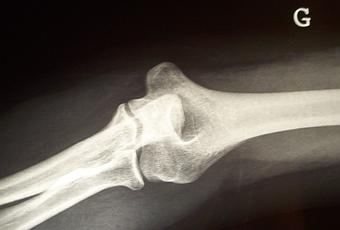

Bon, je commence par quelques techniques familières utilisant de la lumière, mais pas de la lumière visible.Vous êtes tous allé chez un radiologue pour faire une radio (sauf si vous êtes un veinard ou que vous prenez d'incroyables précautions dès que vous sortez de chez vous).

Une radio, ce n'est rien d'autre qu'une image obtenue avec des rayons X. Or les rayons X, comme la lumière visible, ce sont des ondes électromagnétiques. Les rayons X sont donc une forme de "lumière", bien pratique puisqu'elle pénètre facilement dans les tissus mous.Mais, me direz-vous, si c'est de la lumière, comment se fait-il qu'on ne la voie pas ? Bonne question.